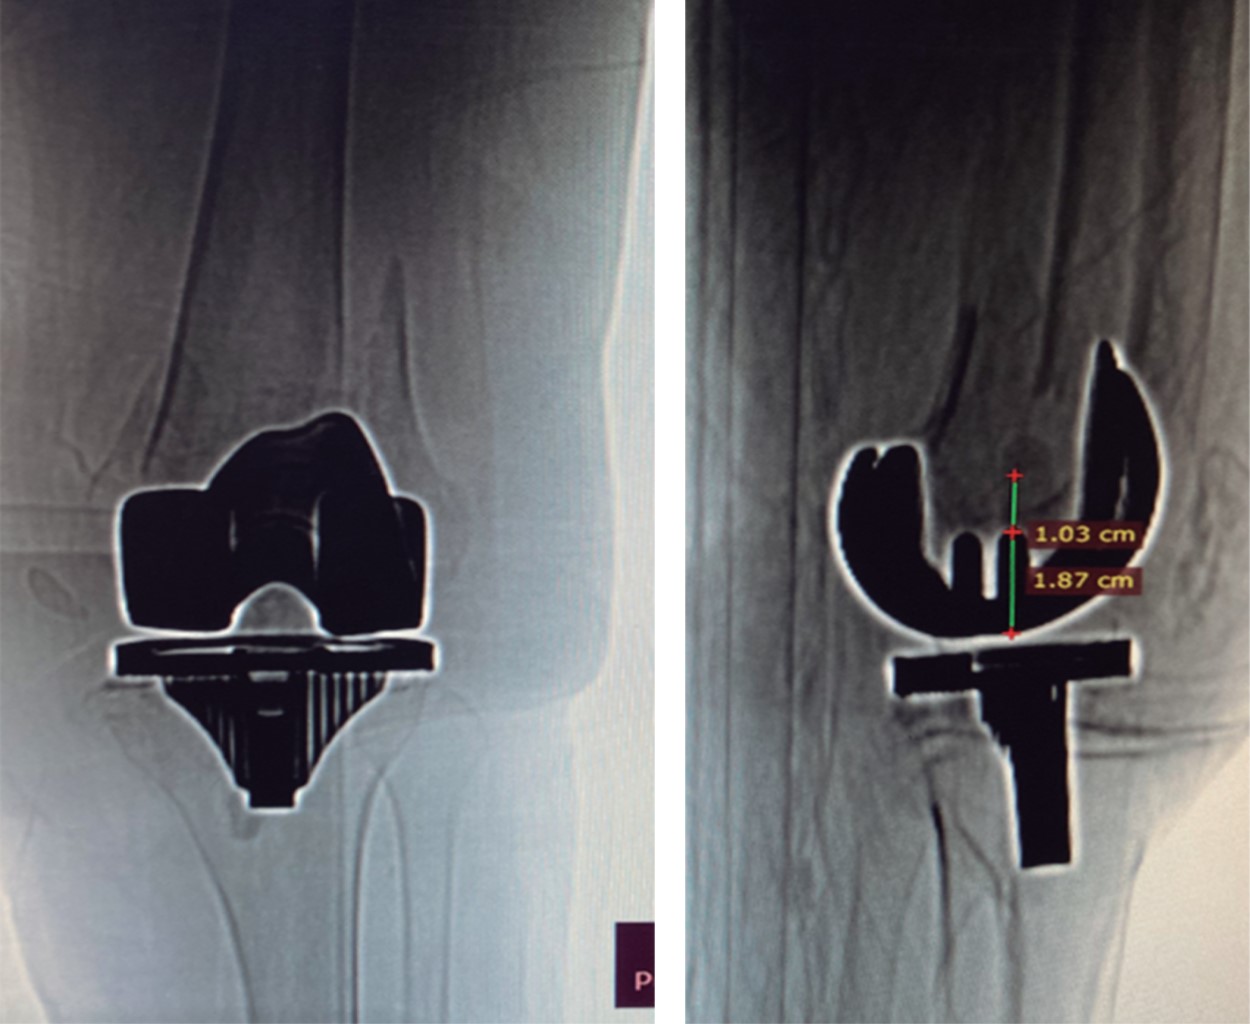

Figure 2